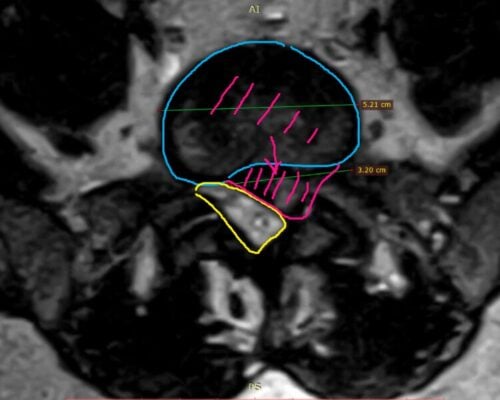

Hernia de disc lombară recidivată este o cauză frecventă de durere persistentă după intervenții chirurgicale ale coloanei. Acest caz evidențiază beneficiile unei abordări moderne, minim invazive, în tratamentul acestei patologii complexe. Contextul pacientului Pacientul este un bărbat activ, în vârstă de 35 de ani, din București, cu antecedente de intervenție chirurgicală lombară. Deși inițial a […]